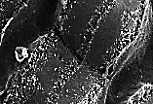

扫描电镜(MEB)下观察肝板断面,可见肝细胞的血窦面布满微绒毛, 胆小管面较光滑,有胆小管穿行且胆小管内也布满微绒毛。

肝血窦 可通过不连续的管壁和大小不等的窗孔识别;

血窦内皮直接贴附于肝细胞血管面的微绒毛上。

血窦内皮与肝细胞微绒毛之间存在狭小的间隙,即狄氏间隙(Disse间隙);该间隙仅能在透射电镜下观察到。

该视野清晰显示肝血窦内皮的窗孔,以及狄氏间隙;肝细胞微绒毛浸泡于狄氏间隙的液体中。